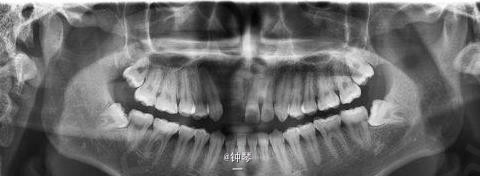

前牙种植+钛网应用

患者,女,30岁,右上1,2缺失要求种植。平素体质一般,否认高血压、糖尿病及心脏病史,否认肝炎、结核病史,无药物、食物过敏史,无外伤、手术及输血史。